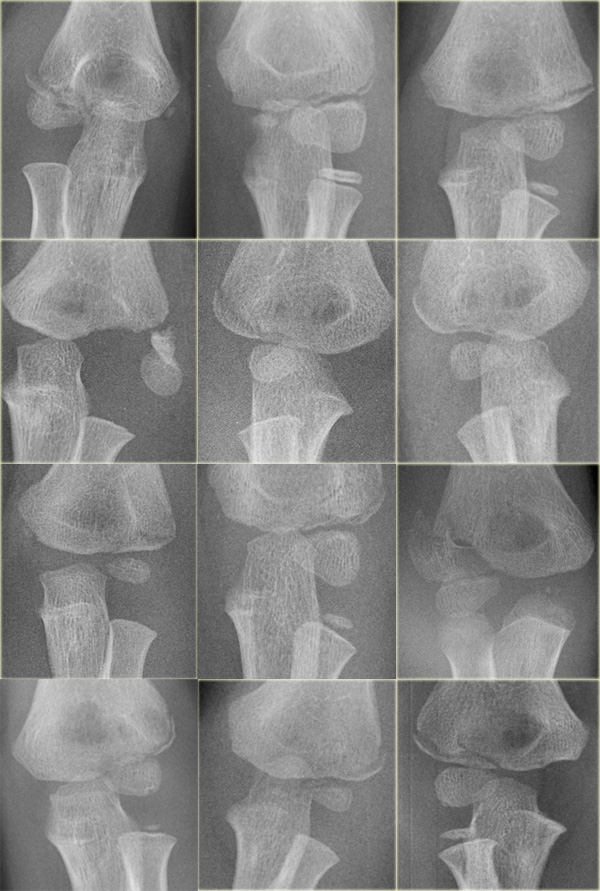

Ossification centres

There are 6 ossification centres around the elbow joint.

They appear and fuse to the adjacent bones at different ages.

It is important to know the sequence of appearance since the ossification centers always appear in a strict order.

This order of appearance is specified in the mnemonic C-R-I-T-O-E (Capitellum - Radius - Internal or medial epicondyle - Trochlea - Olecranon - External or lateral epicondyle).

The ages at which these ossification centres appear are highly variable and differ between individuals.

It is not important to know these ages, but as a general guide you could remember 1-3-5-7-9-11 years.

Fragmented appearance of the Trochlea in 2 different children. Fragmented appearance of the Trochlea in 2 different children.

The Trochlea has two or more ossification centres which can give the trochlea a fragmented appearance.

Trochlea ossification-fragments simulate loose bodies in the joint Trochlea ossification-fragments simulate loose bodies in the joint

On a lateral view the trochlea ossifications may project into the joint.

They should not be mistaken for loose intra-articular bodies (arrow).